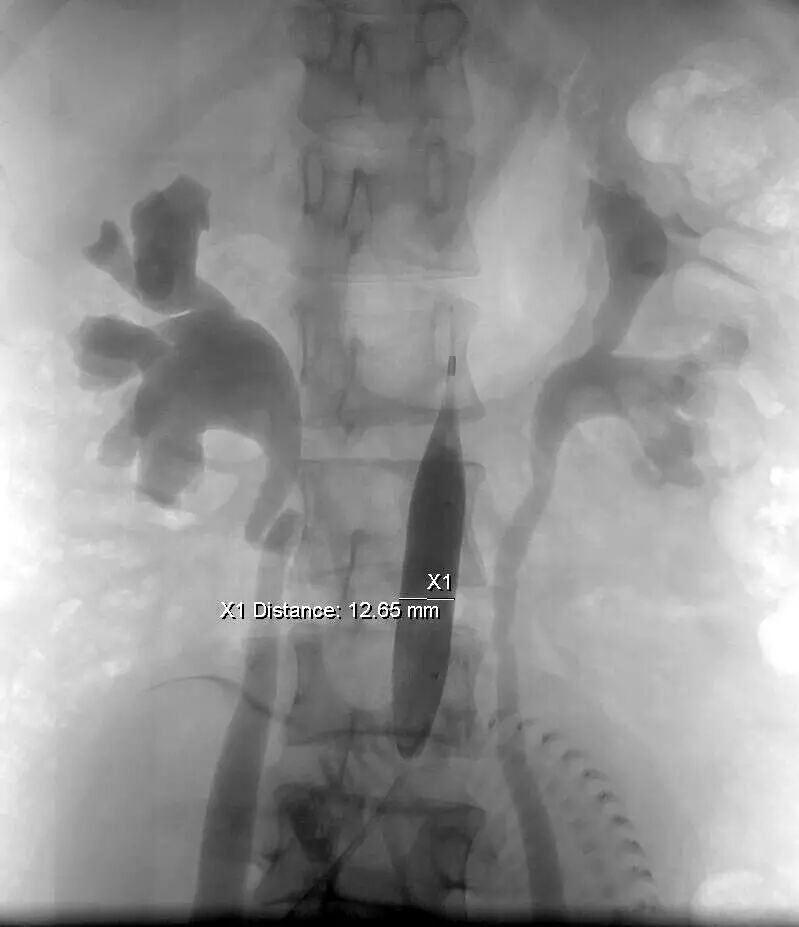

当双侧的子宫动脉栓塞结束后,小BABY已经没有了胎动,说到这读者应该明白是怎么回事了,凶险型前置胎盘伴胎盘植入者剖宫产术中平均出血量高达3000~5000 ml,甚至高达10000 ml以上,严重威胁孕产妇生命安全。既往凶险性前置胎盘剖宫产术后为止血而切除子宫,术中平均失血量仍达为3000-5000ml。为减少出血保留子宫,产科以往采取结扎髂内动脉或子宫动脉,然而对于凶险性前置胎盘并伴有胎盘植入的患者,即使结扎髂内或子宫动脉,也无法完全阻断胎盘植入部位的血供,并且剖宫产术中因出血量大,行髂内或子宫动脉结扎难度增大。近年来球囊导管技术已越来越多的应用于凶险型前置胎盘伴胎盘植入剖宫产术。由于孩子太大避免手术出血过多介入科医生在腹主动脉双侧肾动脉下方放置了球囊导管阻断腹主动脉下端的血供图二。

图二:球囊导管置入

图二:猪尾导管造影定位

图二:球囊导管置入,阻断

一切准备好后直接把病人接到手术室进行清宫,介入医生随从在剖宫产手术过程中根据情况10分钟之内释放球囊一次,即可避免肾脏、下肢、盆腔脏器的缺血,同时可观察胎盘附着面缝合止血情况;若松弛球囊创面未再出血,即可停止球囊应用,并判定缝合子宫止血成功。手术过程出血50ml,手术结束后介入科医生把球囊导管取出,患者安全回病房。